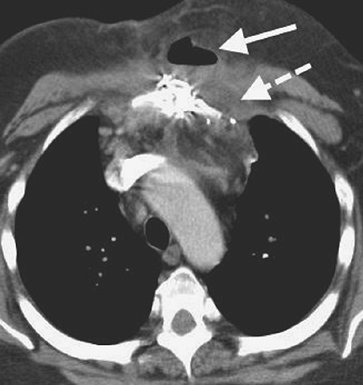

P.145

morphology (irregular thickening and focal masses suggest malignancy), evaluation of underlying parenchymal disease, and differentiation between pleural and parenchymal disease (aided by the use of intravenous contrast material). The attenuation value of pleural fluid on CT enables detection of a hemothorax (Fig. 9-10), which has a higher attenuation value than simple fluid; occasionally, a fluid–fluid or hematocrit level can be seen (see Fig. 8-24). [AU: Did you intend to refer to Fig. ‘8-34’ here, rather than Fig. 8-24 (the latter shows a diaphragm rupture, whereas the former shows a hemothorax)?]

FIGURE 9-10. Hemothorax. CT shows high-attenuation blood (H) in the right pleural space.